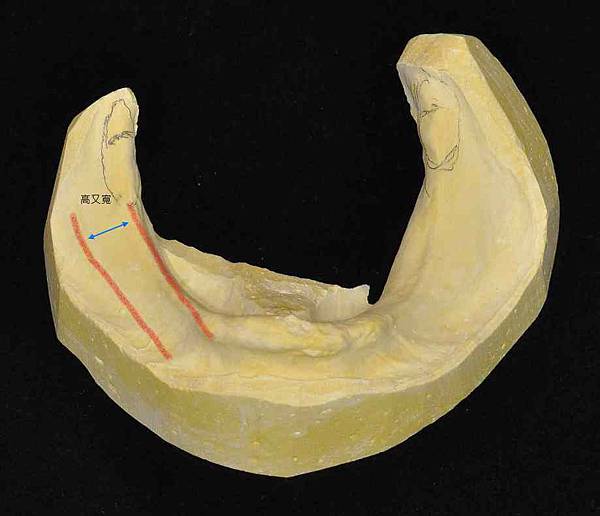

其實一副活動假牙要做多久並沒有標準答案,每個醫師有他習慣的做法,又依不同的醫療系統、設備或需要的治療等等有很多不同的過程。我先就教科書教的大致說明一下流程。按照牙醫教科書來說,做一副活動假牙大概分成五個步驟。分別是:一、取初模分析,二、牙齒修磨並使用個人牙托取主模,三、試金屬床並取咬合關係,四、試牙齒排列蠟型,五、完成,裝戴假牙。每次門診後通常都需要一些後製,如分析、送技工、模型處理等等需要幾個工作天才能約下一次門診。所以每次門診的間隔從幾天到幾星期都有可能。